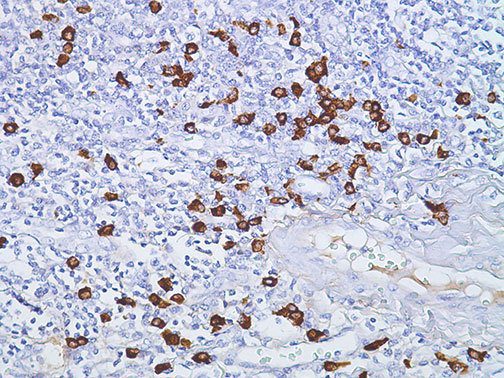

It is the ICU physician who is most likely to witness one of the deadliest manifestations of the abnormal immunological response, the cytokine storm syndrome (CSS). This response is also referred to by some as the cytokine release syndrome (CRS). CSS is characterized by continuous activation and expansion of macrophage and lymphocyte populations, which secrete large amounts of cytokines, causing the cytokine storm. This massive cytokine release is akin to hemophagocytic lymphohistiocytosis (HLH) disease, a syndrome characterized by initial unchecked and persistent activation of cytotoxic T lymphocytes and NK cells.

Clinical and laboratory manifestations of HLH include fever, enlarged liver and/or spleen, neurologic dysfunction, coagulopathy, liver dysfunction, cytopenias (i.e., low levels of erythrocytes, leukocytes, and/or platelets), hypertriglyceridemia, hyperferritinemia, hemophagocytosis, and eventually diminished NK cell activity as the immune system becomes progressively paralyzed. HLH can be familial (primary HLH) or secondary to another disease process (sHLH), such as rheumatic disease, in which it is referred to as macrophage activation syndrome (MAS, characterized by elevated ferritin).